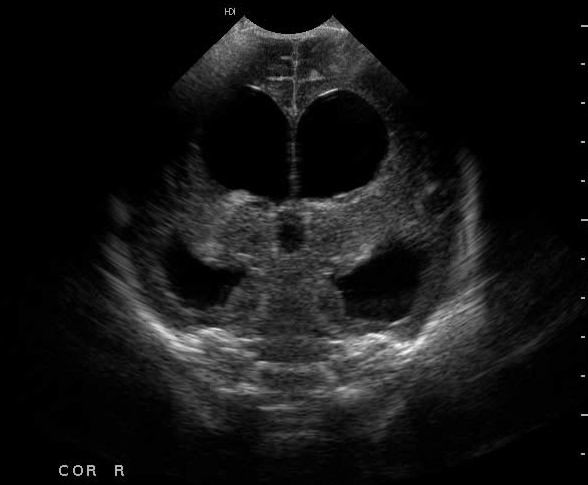

+ Siêu âm thai: Thai 27 tuần, giãn não thất, dịch màng phổi 2 bên, nghi ngờ bất thường tim, thiểu ối.

- Chẩn đoán: Đái tháo đường/thai 27 tuần nghi dị tật thai/Suy giáp sau điều trị I131.